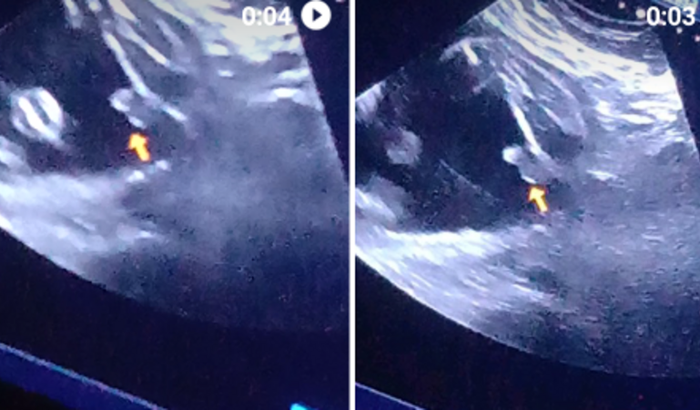

Para fazer uma ultrassom fiscal duas uma deu menina outra deu menino não tenho como paga e a medica não vai pedi mais

Oi me chamo Angelica e estou pedindo ajuda fiz uma utrasom e deu menina e a outra deu menino e a medic nao vai pedir mais e so tenho roupa de menina queria ter certeza me ajudem por favor  ver tudo

Oi me chamo Angelica e estou pedindo ajuda fiz uma utrasom e deu menina e a outra deu menino e a medic nao vai pedir mais e so tenho roupa de menina queria ter certeza me ajudem por favor